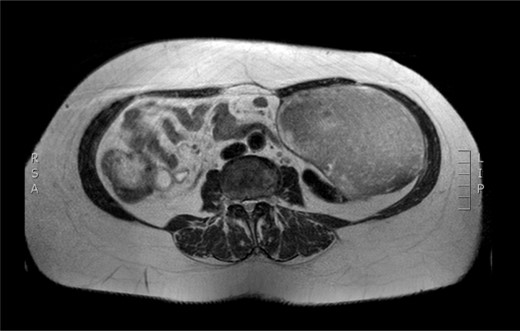

Physical examination revealed a painless, mobile parietal mass on the left anterior abdominal wall, more prominent during cough, of ~13 cm in diameter, with smooth contour and without skin involvement. Laboratory examination including cancer marks showed results within normal limits; hydatid serology (IgG antibodies) was also negative. As ultrasonography results were inconclusive, further imaging with magnetic resonance imaging (MRI) revealed a sizable cystic mass measuring 10 × 13.4 × 11.7 cm, located in the left anterior abdominal quadrant, in the paraumbilical region, between the left internal oblique and the transversus oblique muscle, with projection to the inferior surface of the rectus abdominis. The mass was characterized as a thin-walled cystic lesion, with delayed uptake of intravenous contrast of the wall. High signal intensity was observed on T1-weighted images and low signal intensity on T2-weighted images, with high probability of neoplasia or bleeding (Figs 1–3). No other abdominal or pulmonary lesions were present.

Preoperative MRI. T2 weighted image. Low sign density of the lesion.

The diagnosis of hydatid disease relies on clinical findings, imaging techniques and serology. MRI findings, in particular, that are consistent with hydatid cyst include low-signal-intensity rim on T2-weighted images, which represents the collagen-rich pericyst, whereas cyst material presents hypointense, relative on T1- weighted images and hyperintense on T2- weighted images. Abscess, persistent hematoma, synovial cyst and neoplasia, such as sarcoma and liposarcoma, should be included in the differential diagnosis [4, 5]. Our patient lived in an endemic rural area; however, no previous history of hydatid disease was present, while serology and MRI findings were inconclusive, therefore preoperative diagnosis, could not be precise.